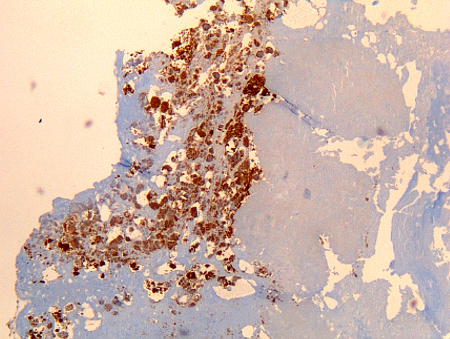

იმუნოჰისტოქიმია

ტესტი

ითვლება Coxiella burnetii-ის ოქროს სტანდარტის ტესტად, თუმცა სრულდება მხოლოდ სპეციალიზებულ ლაბორატორიებში.

იმუნოჰისტოქიმიას აქვს ბაქტერიული ინფექციის სხვადასხვა უჯრედული ტიპების იდენტიფიცირების უპირატესობა, თუმცა ისეთივე სენსიტიური არ არის, როგორც ფლუორესცენტული ინ სიტუ ჰიბრიდიზაცია (FISH).[Figure caption and citation for the preceding image starts]: Coxiella burnetii ოსტეიტი: იმუნოჰისტოქიმია: ყავისფერი შეფერილობა ავლენს ბაქტერიას მონოციტებში/მაკროფაგებშიHubert Lepidi, Institut Hospitalo-Universitaire Méditerranée Infection [Citation ends].